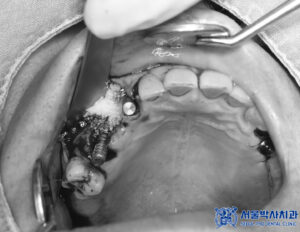

이후 발치 후 상악동거상술과

뼈이식을 동반한

무절개임플란트 수술을

진행하였습니다.

위, 아래 총 9개의

임플란트 식립이

이루어졌습니다.

<무절개임플란트>

컴퓨터 분석을 통해

미리 계산된 경로를 활용하여

임플란트 식립 오차가 줄어들며,

수슬 가이드를 활용하여

침습 범위가 매우 적습니다.

위의 사진과 같이

수술 가이드처럼 유도장치를

착영하고 수술을 진행하며,

위 장치는 고성능 3D 프린터로

컴퓨터 분석으로 정밀한

계산을 통해 제작됩니다.